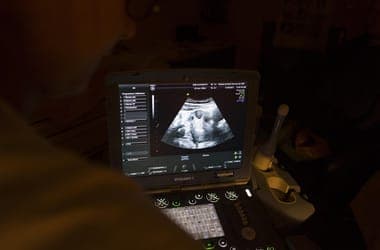

Fetal Stem Cell Therapy for Spina Bifida Shows Promise in Trials

Initial trials of a stem cell therapy for spina bifida performed on fetuses have proven safe, offering potential to significantly improve the lives of many children in the future.